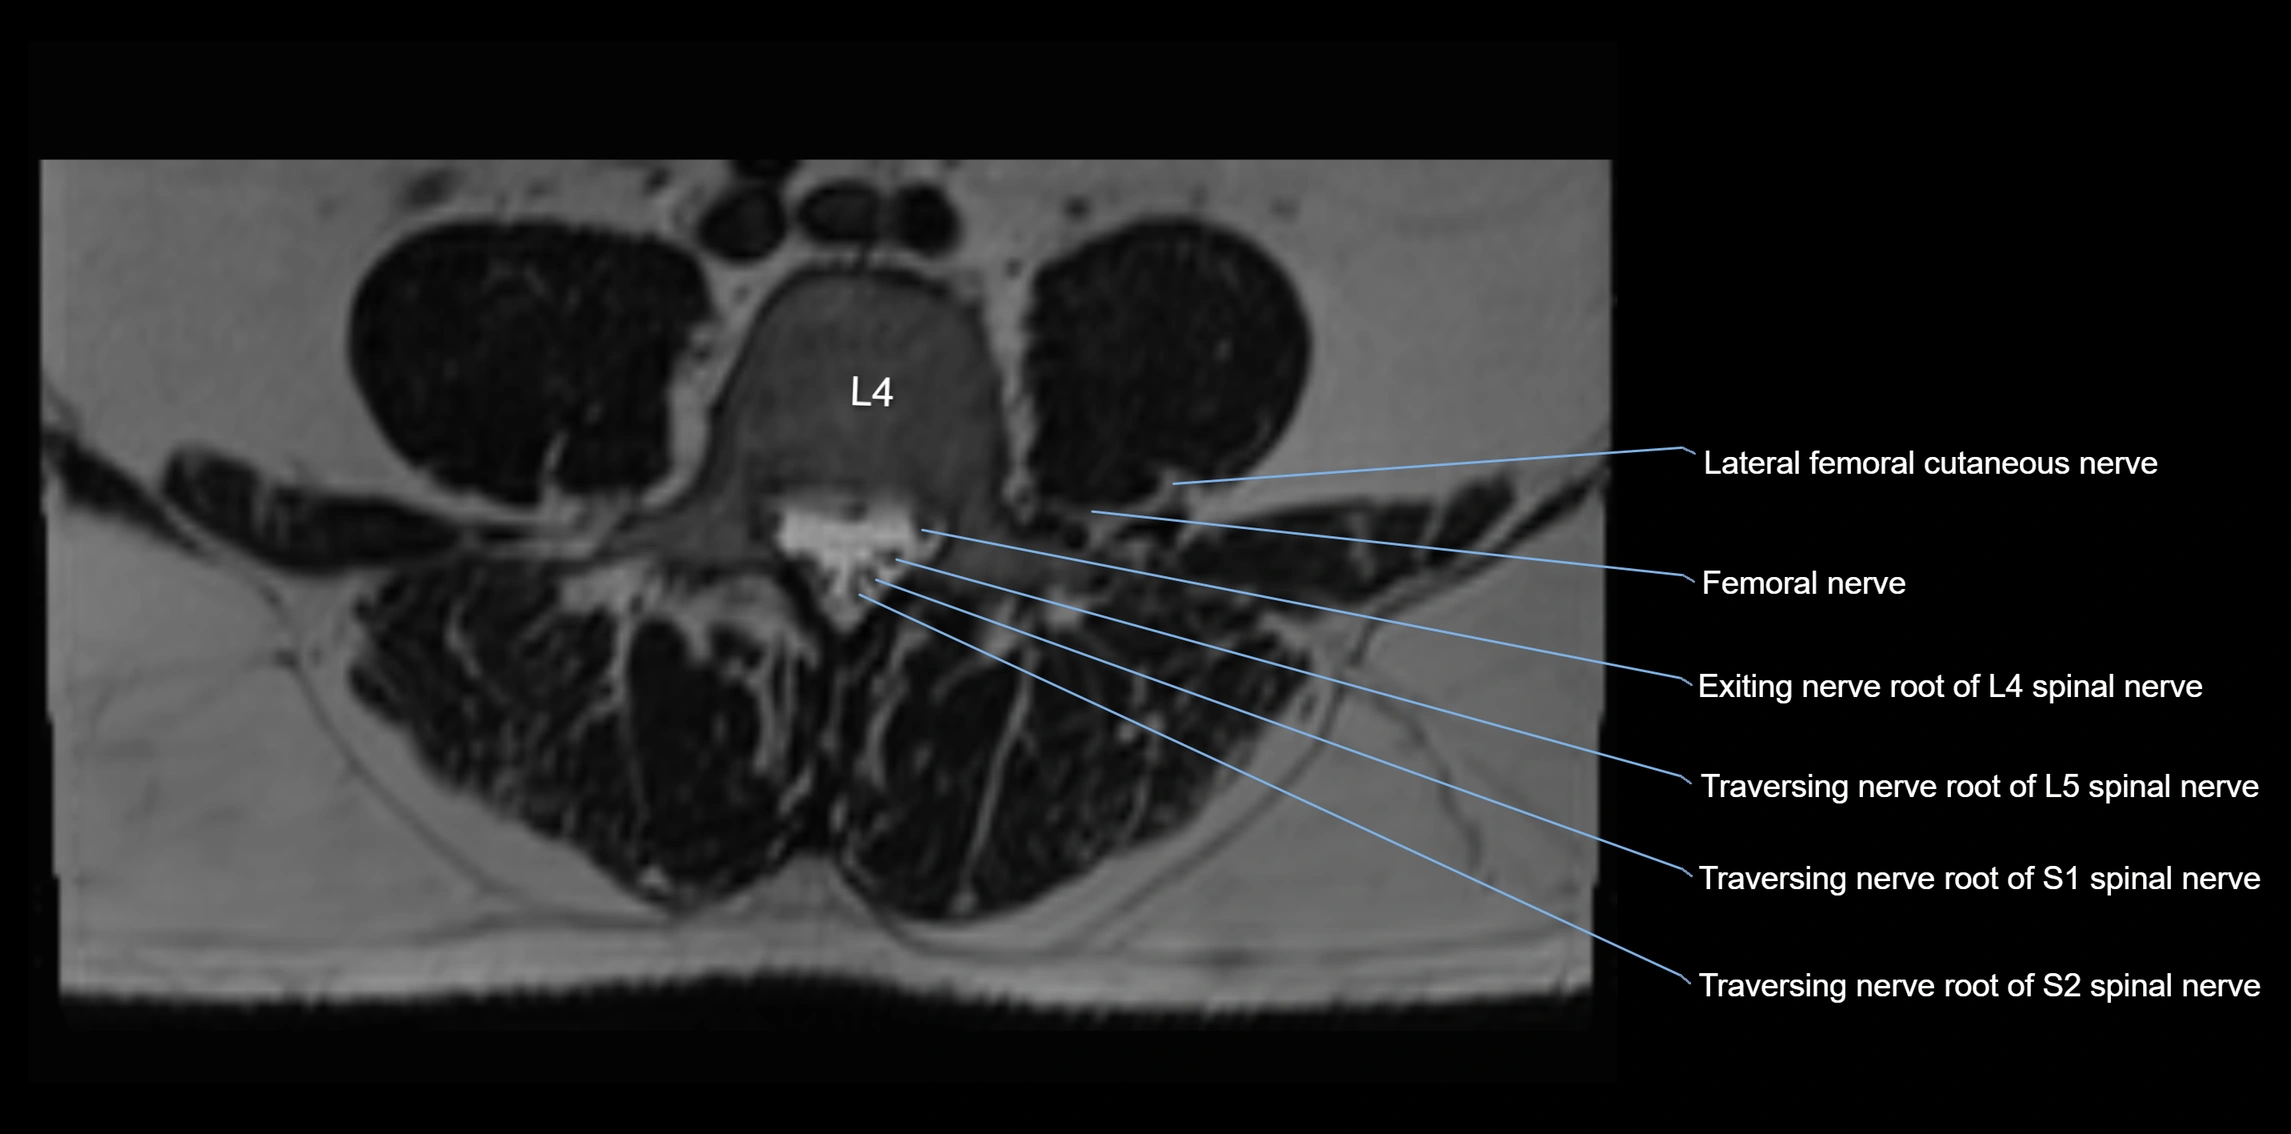

MRI image

image